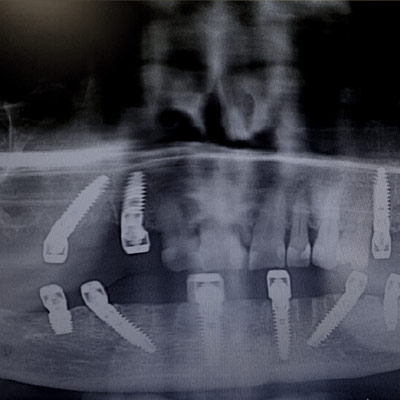

Secondo modulo

Chirurgia avanzata: Rigenerativa vs bypass

Corso teorico – pratico che ti consentirà  di gestire il paziente nelle diverse fasi di riabilitazione: approccio conservativo Vs sostitutivo; post – estrattivi immediati o differiti; carico immediato o ritardato.

L’ABC del diagramma di flusso decisionale in implanto – protesi.